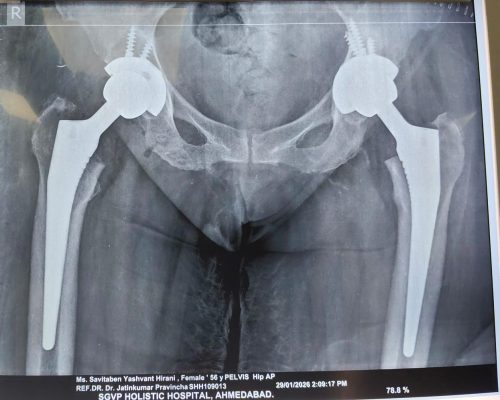

Total Hip Replacement

A total hip replacement, also known as a total hip arthroplasty, involves surgically removing the damaged or diseased hip joint and replacing it with a prosthetic implant. This procedure is commonly performed to relieve pain and improve mobility in individuals suffering from conditions like osteoarthritis, rheumatoid arthritis, or hip fractures. Dr. Jatin Vadodariya is a well-experienced Hip Replacement Doctor in Ahmedabad, Gujarat, Rajasthan.